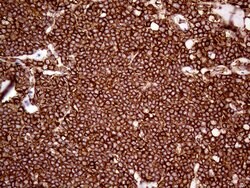

| Immunohistochemistry (Paraffin), Western Blot | |